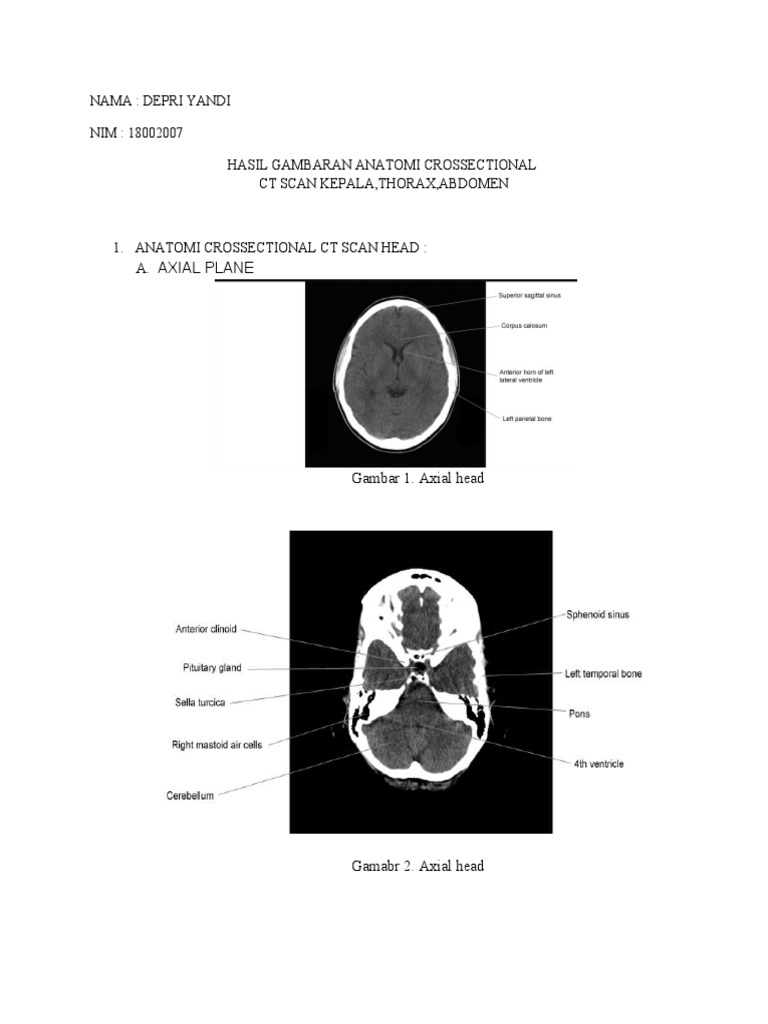

Coronal head ( potongan coronal dari kepala ). Dural venous sinuses, veins, arteries. Untuk bisa membaca ct scan, kamu harus tau anatomi kepala, ya! Ct scan kepala menginformasikan tentang kondisi mata, tulang rahang, sinus hidung, dan bagian dalam telinga.